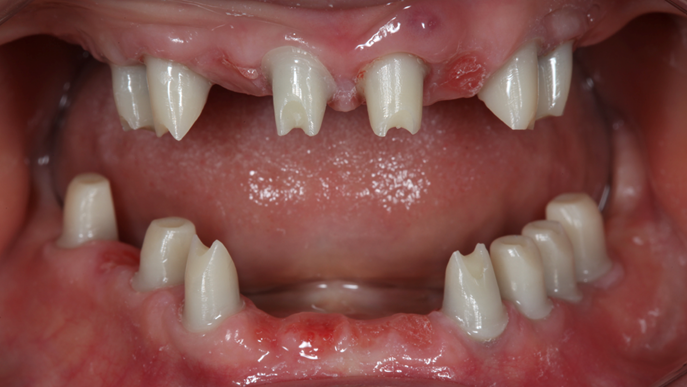

- Courtesy of Dr. Jong Cheol Kim, Korea

Effective R2STUDIO in complex tooth positioning